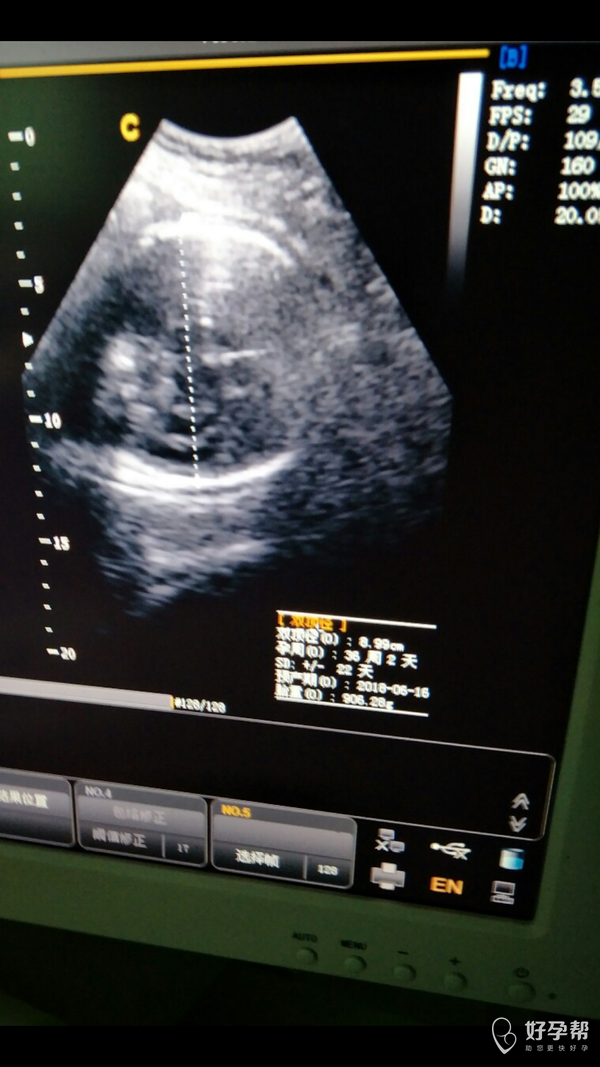

医生帮忙看下这个几个数据是什么意思